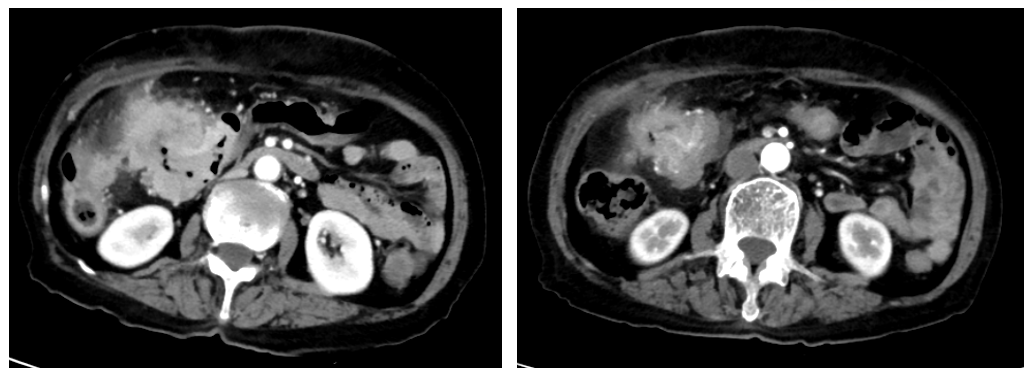

2022年8月24日行胸腹部CT检查:结肠癌化疗后,病灶范围较前缩小(现最厚处约2.7cm,累及长度约7.4cm),周围肠系膜多发淋巴结转移,较前缩小,右腹壁病灶明显缩小;双肺多发小结节,部分磨玻璃结节(现大者位于右肺中叶,径约0.5cm),部分较前显示不清,余较前相仿,建议随诊(图5)。疗效评价:PR。

2022年10月27日行胸腹部CT检查:结肠癌化疗后,病灶范围较前大致相仿(现最厚处约2.7cm,累及长度约7.4cm);周围肠系膜多发淋巴结,较前相仿;双肺多发小结节,部分磨玻璃结节(大者位于右肺中叶,径约0.5cm),较前相仿,建议随诊。疗效评价:SD。

2022年12月13日行腹部CT检查:结肠癌化疗后,病灶范围较前大致相仿(现最厚处约2.2cm,累及长度约7.5cm);周围肠系膜多发淋巴结,较前相仿。

2023年1月28日行胸腹部CT检查:结肠癌化疗后,病灶范围较前大致相仿(现最厚处约2.1cm,累及长度约7.6cm);周围肠系膜多发淋巴结,较前相仿;双肺多发小结节,较前相仿,建议随诊。

患者于2023年2月6日在全麻下行根治性右半结肠切除术,术中见结肠肝曲肿瘤7*6*5cm,侵出浆膜,并侵及右前腹壁,向后内侧与十二指肠降部及水平部稍有粘连,肠旁未见明显肿大淋巴结。

术后病理:ypT4N0M0 IIb期。